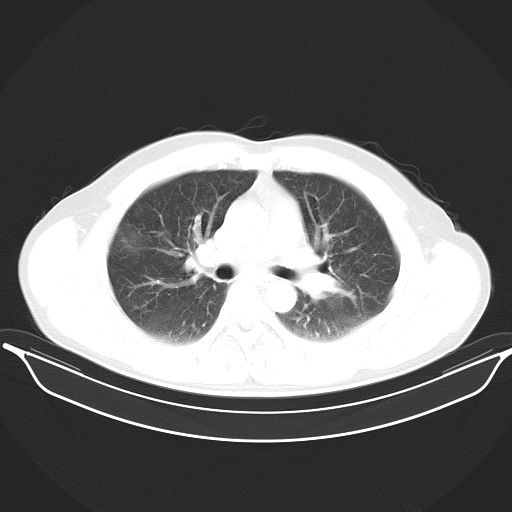

标题: CT25490:男,40岁,体检发现;无其它不适。 [打印本页]

标题: CT25490:男,40岁,体检发现;无其它不适。

考虑右下肺周围性肺癌并肺内多发转移,纵隔淋巴结转移!

支持 !考虑右下肺周围性肺癌并肺内多发转移,纵隔淋巴结转移,(气管前腔静脉后,隆突下,主动脉弓下都有了)